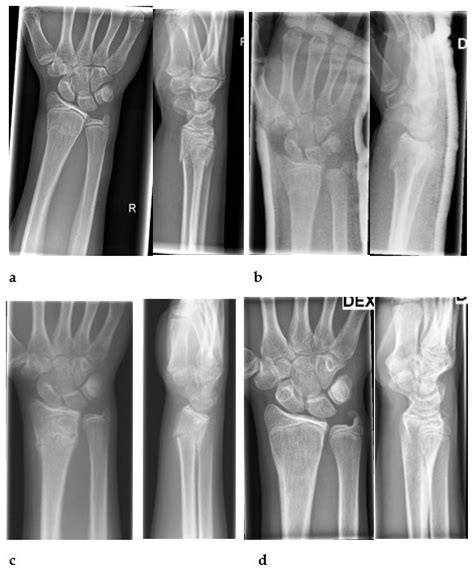

Diagnosing Wrist Fractures

Diagnosing a wrist fracture typically involves a combination of physical examination and imaging tests. Here are the steps involved:

• Physical Examination: A healthcare provider will examine the wrist, checking for pain, swelling, and deformity.

• X-Rays: X-rays are the primary imaging test used to diagnose wrist fractures. They can show the location and severity of the break.

• CT Scans: In some cases, a CT scan may be ordered to provide a more detailed view of the fracture.

• MRI: An MRI may be used to assess soft tissue damage and to evaluate the extent of the fracture.